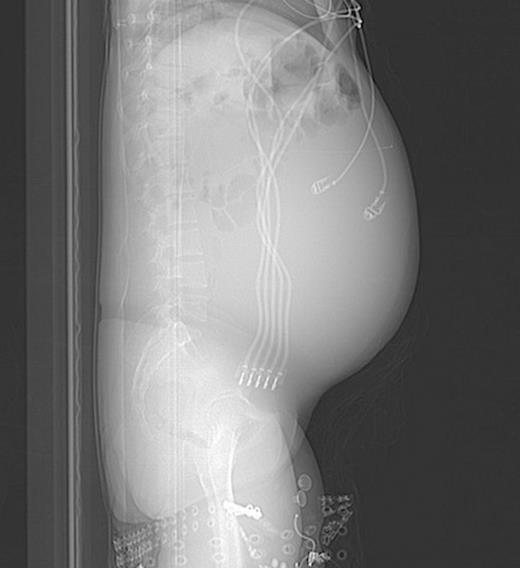

Post-operative abdominal CT demonstrating complete resolution of the fluid compartment

The patient underwent laparoscopic cyst drainage with removal of the cyst wall. A total of 12.7L of fluid was drained. Culture results and routine labs were all negative. A post-operative CT demonstrated complete resolution of the fluid compartment (Fig. 4). The VP shunt catheter was initially left in the abdominal cavity. One month later, however, she developed significant recurrence of fluid collection (Fig. 5) and lethargy from malfunction of the VP shunt. The recurrent fluid was drained under ultrasound guidance, and her abdominal shunt catheter was removed. A new shunt catheter was placed in the right atrium, and the patient made a full recovery without any further complications.